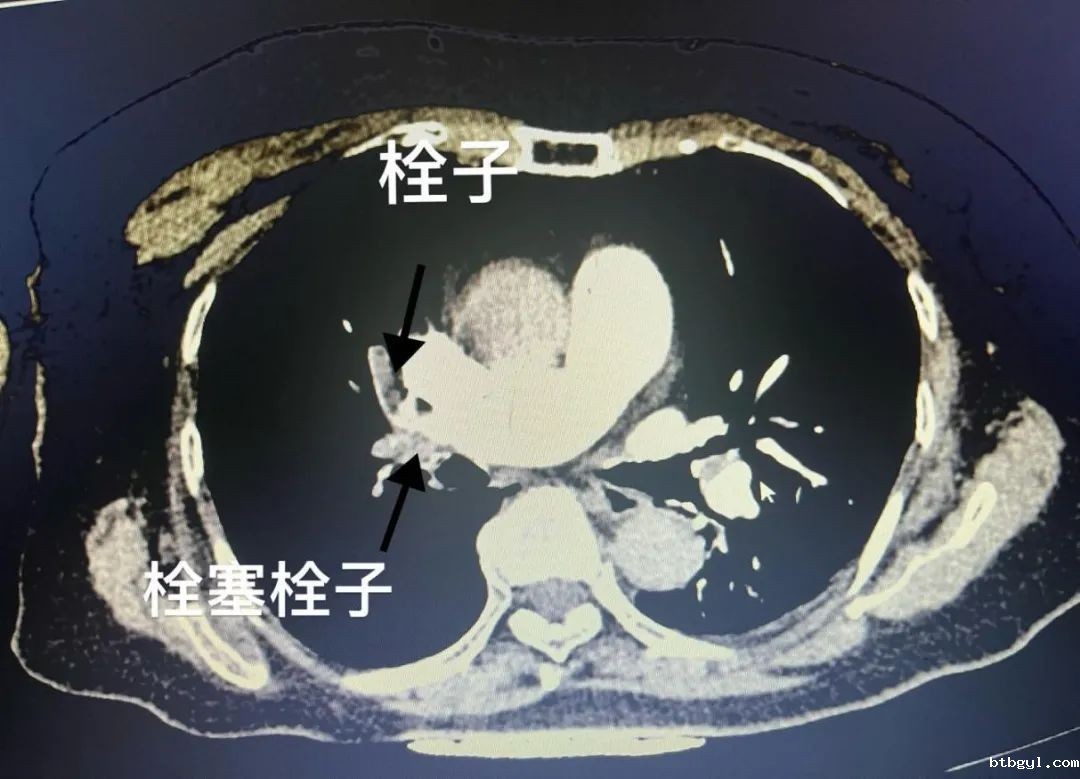

近日,74岁的何婆婆在平路慢行时出现呼吸困难,胸闷、心悸等症状,剑突下伴压榨感,于是到必威betway西汉姆联官方网站急诊医学科就诊。医生考虑为急性肺动脉栓塞,在询问病史、完善相关检查后证实该诊断。

医生向患者家属沟通该疾病的潜在风险及治疗方案后,患者家属立即选择行下腔静脉滤器置入+肺动脉栓塞取栓溶栓术。 术后继续行标准抗凝治疗,抗凝5天后复查CTPT。 经过血管外科医护的精心治疗,何婆婆顺利出院了,术后继续抗凝3-6月,门诊随访既可。

要确诊肺栓塞,我们需要结合患者的症状,体征和一系列辅助检查。其中,CT肺动脉造影是目前诊断的金标准,如果可以看到动脉分支栓塞,那么就可以诊断为肺栓塞。此外,化验D-二聚体、凝血功能,以及心电图、彩超等也可以作为辅助诊断手段。